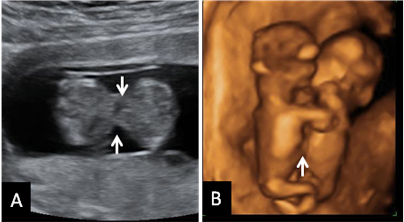

• Flujo patológico en el conducto venoso. Se explora el flujo sanguíneo fetal, por ecografía Doppler, a través de esta estructura vascular, que comunica la vena umbilical con la vena cava inferior. La alteración del flujo sanguíneo a su través (ausencia o inversión de flujo en la onda a) ocurre en un 69% de niños con síndrome de Down. También aquí debemos recordar que hay un 3,7 % de niños normales que tienen alterado este flujo [Ecografía del flujo patológico]. Este parámetro también puede ser anómalo en fetos con alteraciones cardiacas.

• Insuficiencia tricúspide. Se hace un estudio con ecografía Doppler para ver si esta válvula tiene insuficiencia. Aparece insuficiencia en el 65-70% de los fetos con síndrome de Down. También hasta en un 5% de fetos normales. Como el anterior, puede asociarse a alguna cardiopatía [Ecografía de la insuficiencia tricúspide].